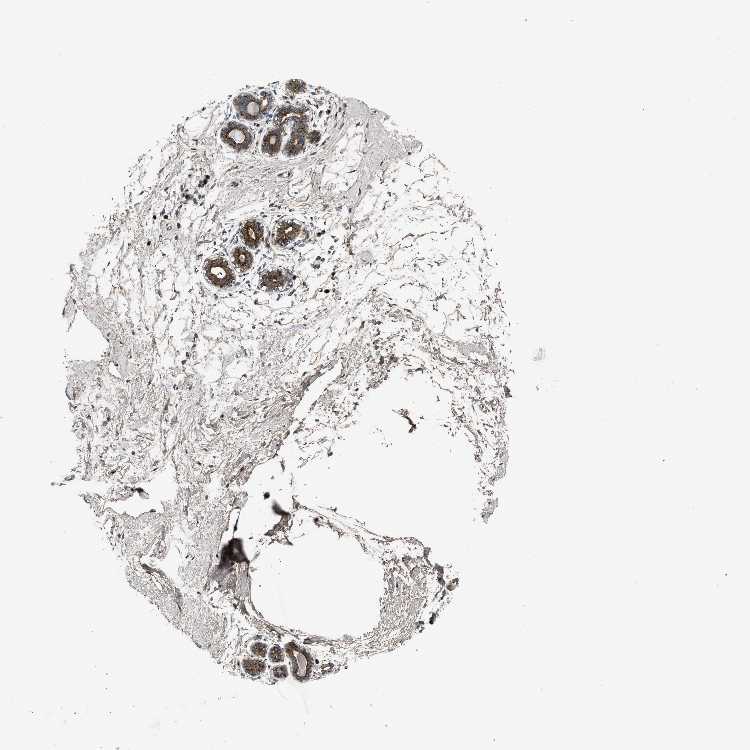

ZNF70